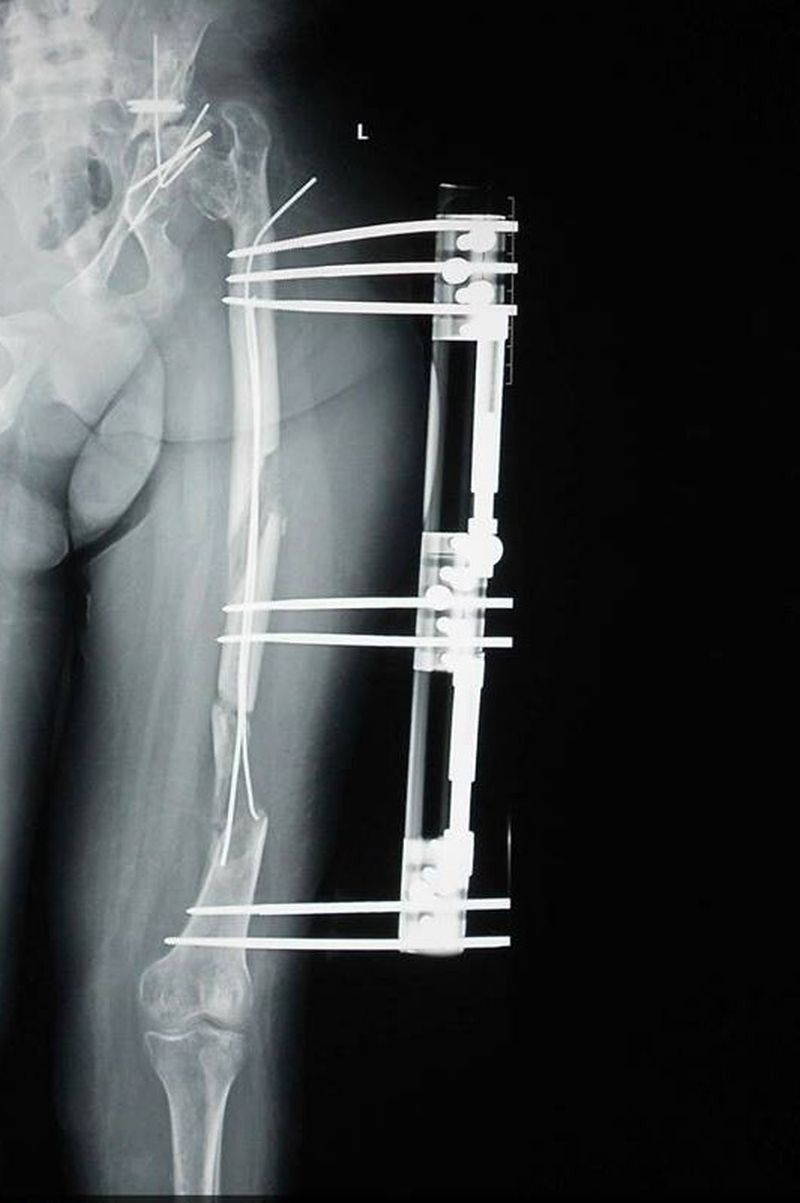

Intregul scandal legat de profesorul Gheorghe Burnei, medicul acuzat ca a facut experimente pe copii saraci, a avut in prim-plan cazul Amirei, o tanara care in ultimii 18 ani a fost operata de 11 ori de celebrul chirurg si a ajuns sa nu mai poata merge. „Experimentul” despre care se vorbeste in articolul de la care a inceput ancheta se numeste Biovitroceramica, omologat (conform casajurnalistului.ro) doar in stomatologie sau diverse tumori osoase.

In cazul Amirei, Burnei avea de efectuat o operatie simpla, de indreptare a bazinului, insa a preferat sa sparga osul si sa-i puna respectivul implant.